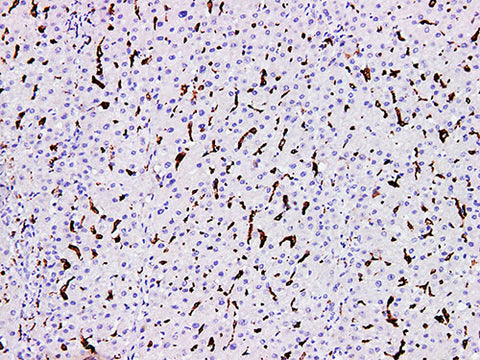

CD163 Monoclonal Antibody Synonyms CD163

Applications IHC-P

Tissue Specificity Liver cancer

CD163 is a type I membrane protein, which belongs to the scavenger receptor superfamily. CD163 is the most specific tissue cell (monocyte and macrophage) marker currently used. It is expressed in peripheral circulating monocytes and macrophages in most tissues, such as spleen dendritic cells, alveolar macrophages, liver Kupffer cells. However, CD163 is not expressed in the immature cells which are in the center of some lymphoid follicles, macrophages, Langerhans cells and finger like reticulocytes. In tumor tissue, CD163 is expressed in monocyte like cells in the majority of AML, as well as in lymphadenopathy, Langerhans cytosis, typical and atypical fibrosarcoma.